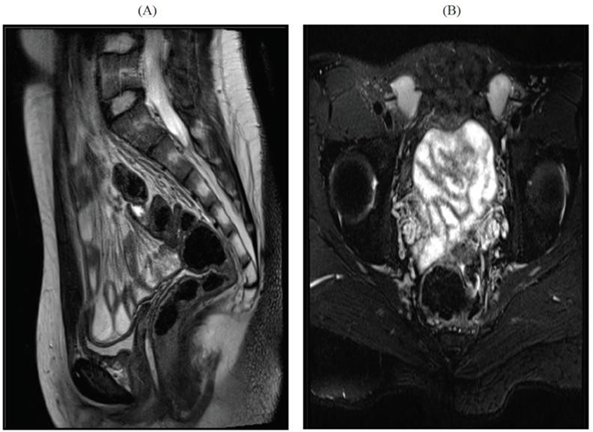

During the period under review, a total of 69 patients with 46 xy dsd were evaluated. Twelve (20.3%) patients, were diagnosed to have 5-α-reductase deficiency, based on hormonal investigations, the (dht/t) ratio, post-hcg stimulation, was high in all patients. Their ages ranged from birth to 12 years. The diagnostic imagings (ultrasound and/or magnetic resonance mr) were utilized to elucidate the internal organs (figures 2 and 3). None of the patients were found to have internal female structures. However all were found to have testes in variable positions (abdomen, inguinal canal and scrotum).

Establishing the diagnosis of 5-α-reductase deficiency is often suggested by an elevated plasma testosterone (t), to dihydrotestosterone (dht) ratio following human chorionic gonadotropin hormone (hcg) stimulation8-10. Genetic studies can confirm the diagnosis11-16. Imaging diagnostic studies with ultrasonography (us) and/or magnetic resonance (mr) will help in elucidating the internal structures. In all patients no female internal organs were demonstrated, however, all were found to have testes in variable positions (abdomen, inguinal canal and scrotum)17-24.